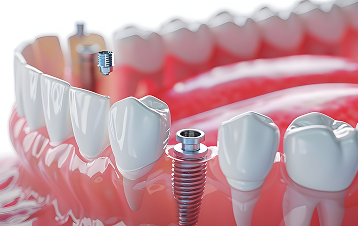

インプラントとは、歯を失った部分にチタン製の人工歯根を埋め込み、その上に歯の形をした上部構造を装着して歯を補う治療法です。

人工歯根は骨としっかり結合するため、硬いものでもしっかり噛むことができます。さらに、取り付ける上部構造にはセラミック素材を使用するため、見た目が自然で、ご自身の歯とほとんど変わらない仕上がりが期待できます。

一次手術(インプラント体埋入)

症例に応じて1回または2回に分けて行います。最初の手術では、歯ぐきを切開し、インプラントの土台となるチタン製のフィクスチャー(人工歯根)を埋め込みます。手術は部分麻酔を使用し、約90分ほどで完了します。その後、歯肉を縫合します。麻酔が切れた後に痛みを感じることがありますが、その際は痛み止めを服用していただきます。

フィクスチャ―が安定すると、再度歯ぐきを切開し、上部構造を取り付けるために長いキャップを装着し、歯茎の形を整えます。

上部構造の取り付け

人工歯を取り付けます。かみ合わせなどを微調整して、インプラント治療は完了です。